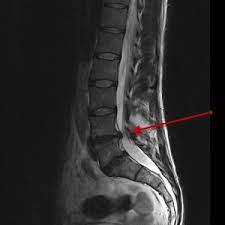

A hérnia de disco ocorre quando o núcleo interno de um disco intervertebral se desloca, pressionando os nervos da coluna vertebral e causando dores intensas. Os sintomas variam de pessoa para pessoa e podem incluir dor irradiante, formigamento, fraqueza muscular e até perda de sensibilidade. Um diagnóstico preciso é fundamental para determinar a abordagem de tratamento mais eficaz.